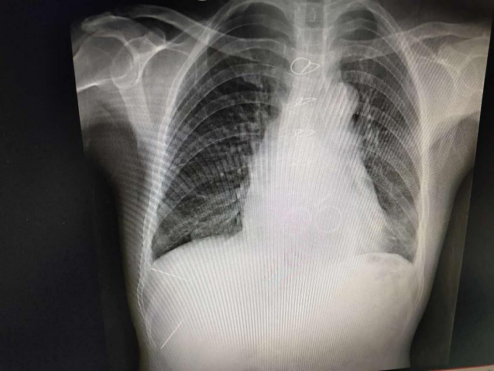

可是近一年来,患者反复出现腹胀、心悸等症状,带着不安再次回到市第一人民医院检查,未曾料想的是心脏彩超提示“三尖瓣中-大量反流”,手术指征明确。但是患者体质差,系心脏瓣膜二次手术,风险大,难度高,术中大出血几率高,术后低心排综合征、心功能衰竭等严重并发症出现的可能性大,死亡率高。经北京常春藤高端医学联盟心脏外科项目李巅远教授团队与市第一人民医院心胸外科张文林主任、张熠副主任医师及团队医生反复商榷,认为此例手术虽然难度大、风险高,但是为了能让患者活下去必须手术。确定后,专家们齐心聚智为患者制定了手术方案,力争把风险降至最低。一切准备就绪,2018年12月30日,患者在体外循环下行三尖瓣机械瓣置换术,手术历时3小时45分,顺利术毕。患者于术后第2天就由重症监护室转入专科病房治疗。目前病情平稳,生命体征正常。

心脏瓣膜病三瓣(主动脉瓣、二尖瓣、三尖瓣)机械瓣置换手术,同时系10年后的二次手术,手术难度大,风险高,死亡率高。手术的成功实施填补了广元此类技术的空白,开创了广元医疗技术的先河,是市第一人民医院心胸外科医疗技术水平已达国内先进水平的又一例证!市第一人民医院心胸外科团队将一如既往、不辱使命、磨砥刻厉造福广元及川陕甘毗邻地区的患者!